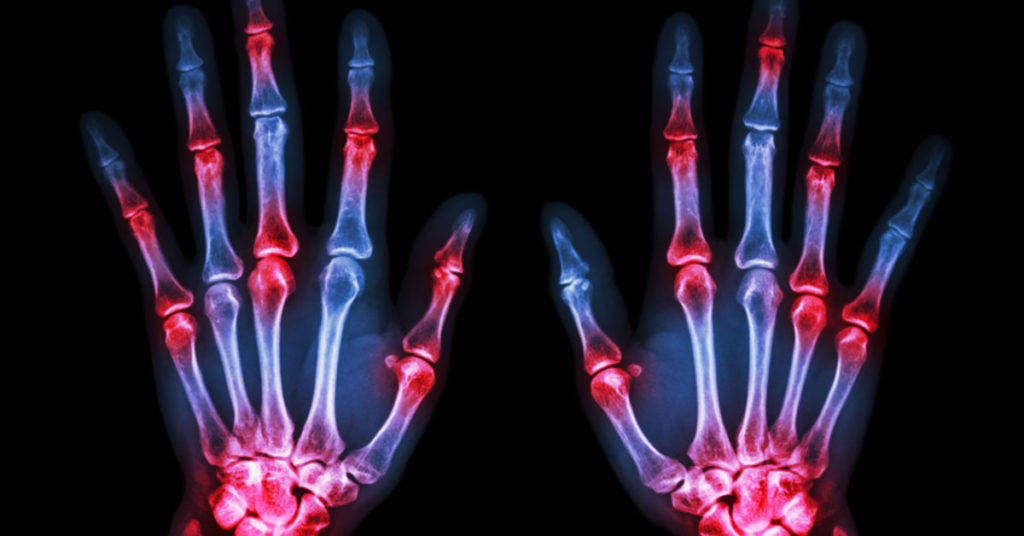

Arthritis Signs and Symptoms August 26, 2020 by Ali Mustafa Arthritis Signs and Symptoms About Ali Mustafa Previous Post:Arthritis Signs & Symptoms